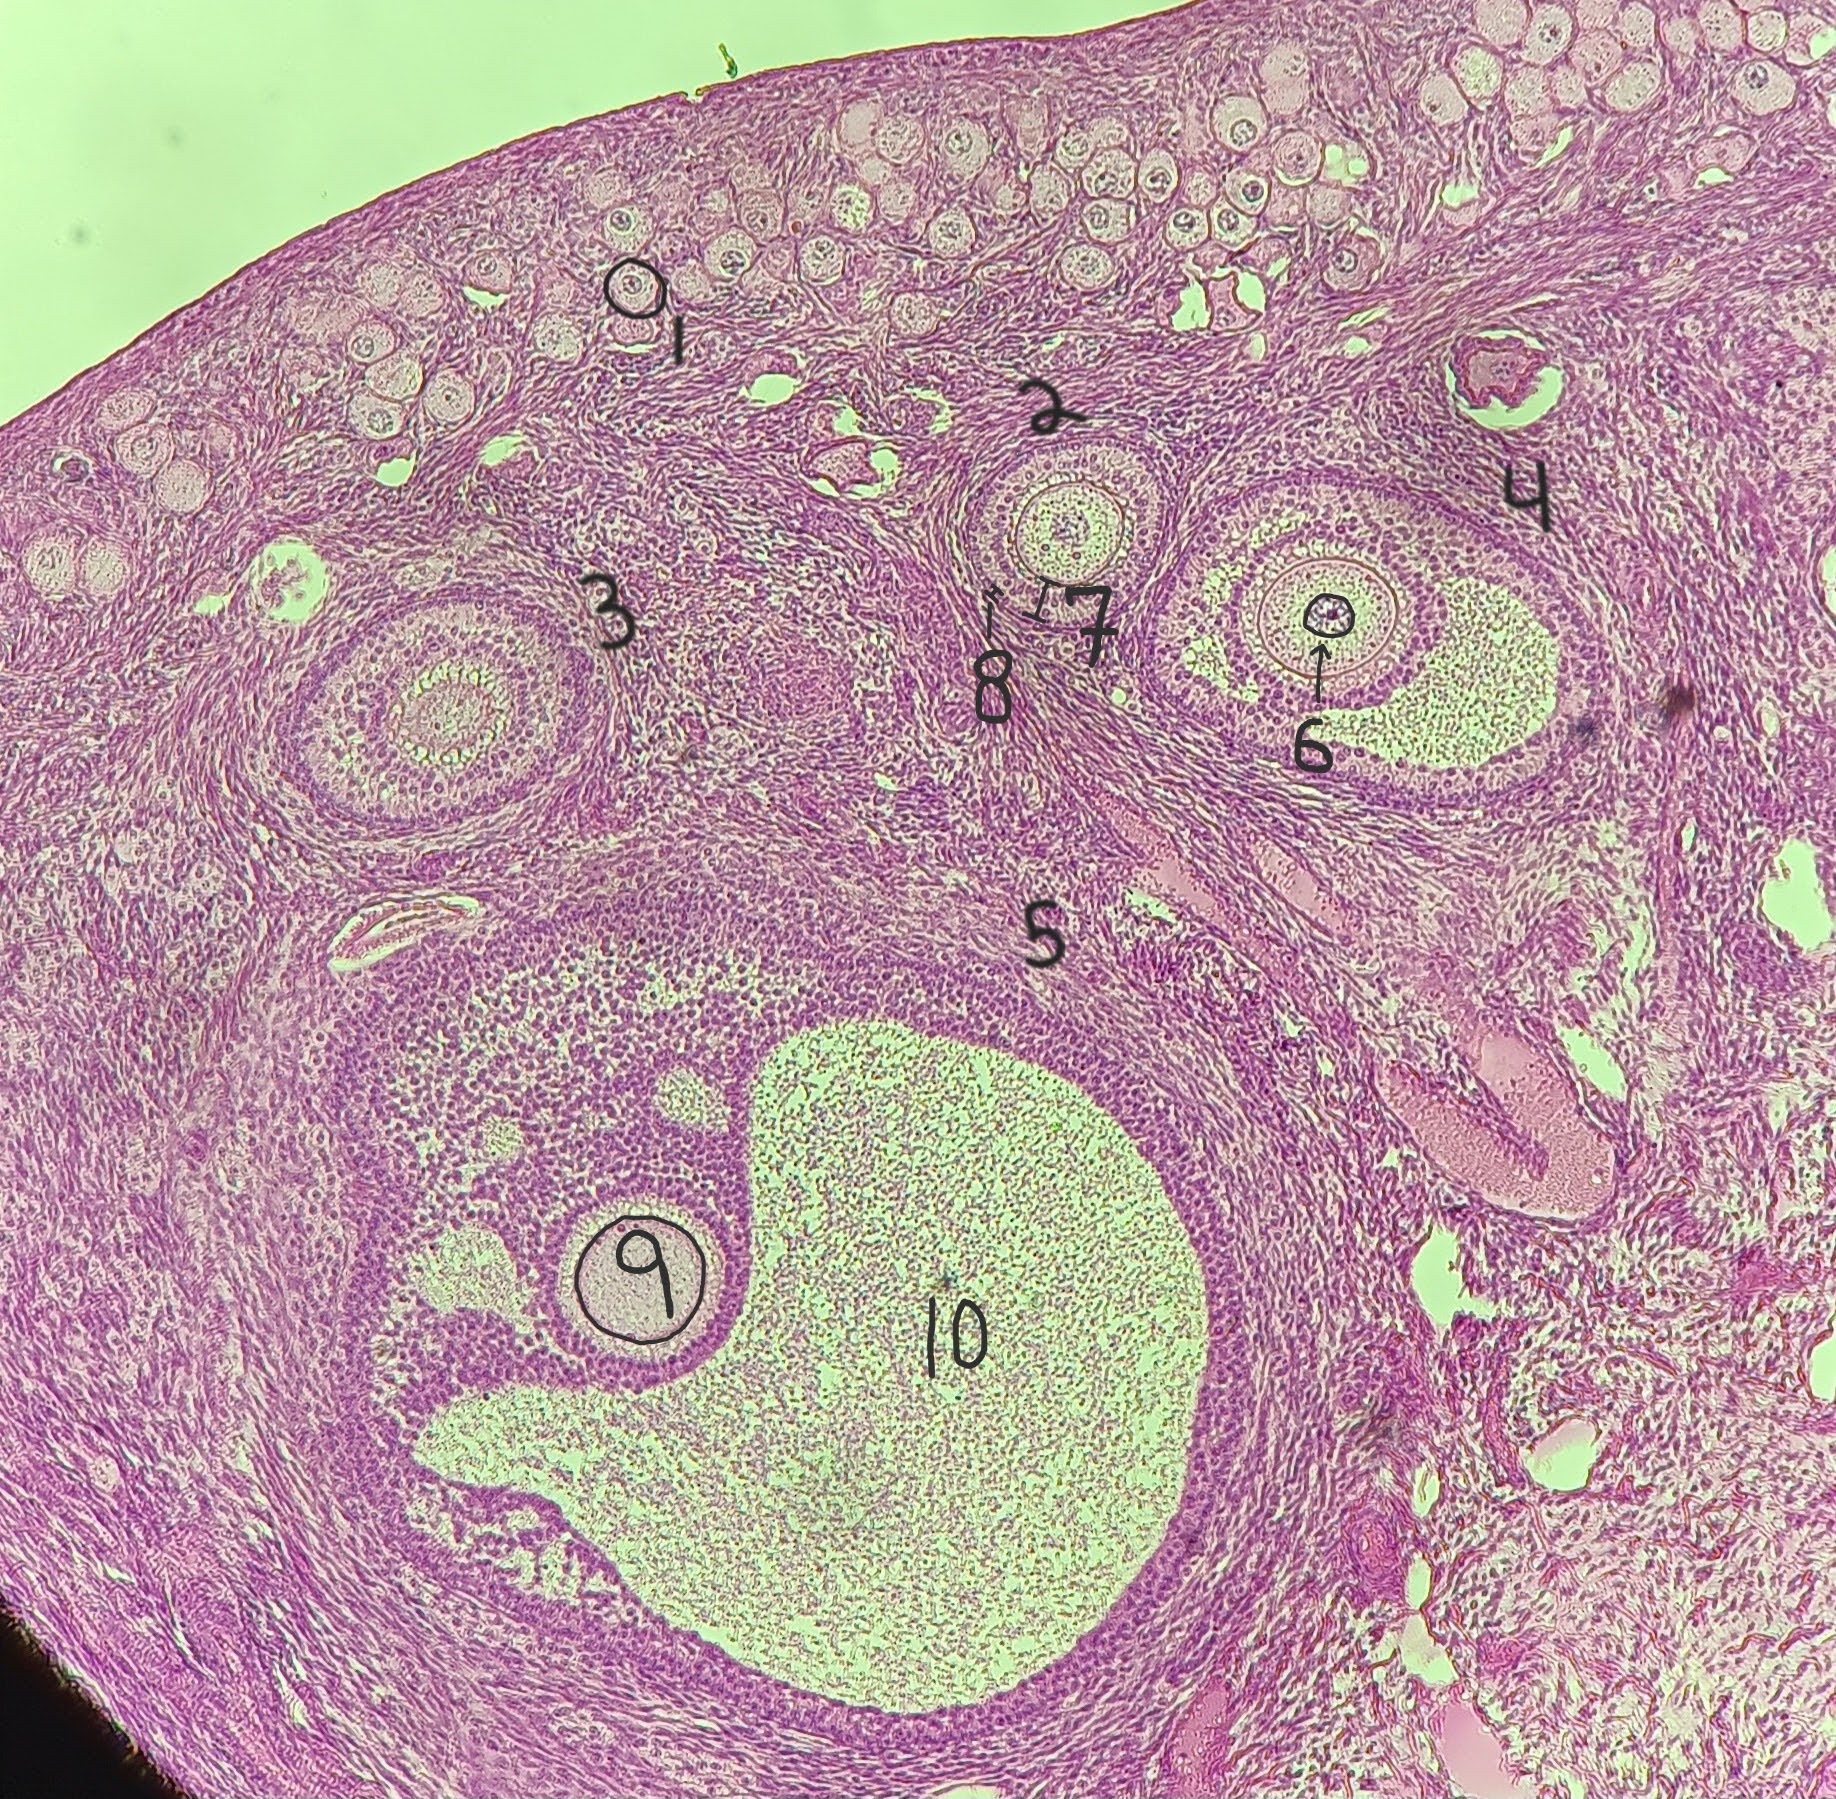

Primordial follicle

1

Primordial follicle

Primordial follicle

1

Primary follicle

2

Primary follicle

Primary follicle

2

Secondary follicle

3

Secondary follicle

Secondary follicle

3

Tertiary follicle

4

Tertiary follicle

4

Mature follicle

5

Mature follicle

Mature follicle

7

Antrum

10

Zona pellucida

9

Theca folliculi

8

Corona radiata

Corpus luteum

Corpus luteum

Corpus albicans

Corpus albicans

corpus luteum

8

early corpus luteum

9

late corpus luteum

10

corpus albicans

11